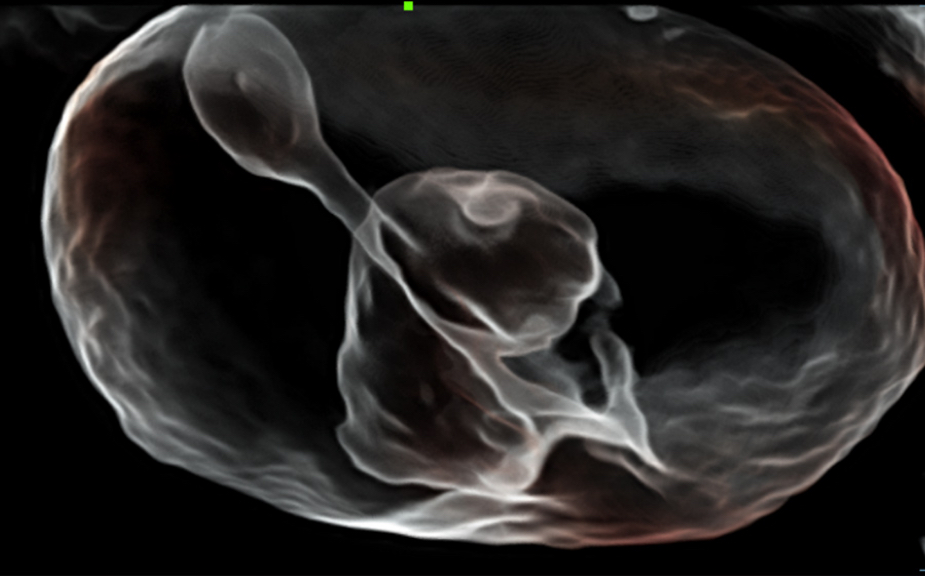

Nuewa I9? ??? ???? ?? ??? ?? ??? ???? ?? ??? ???? ???? ??? ?????. ??? ??? ??? ?? ????? ?? ???? ???? ???? ???? ??? ???? ??? ??? ???? ??? ???? ??? ?? ?????.

ZST+ ???? ???? ??? ???? ??? ?????. ??? ????? ??? ? ???? ?? ??? ?? ????? ?????. ?? ???, ?? ???, ?? ??? ?? ?? ?? ??? ??? ???? ???? ??? ?? ??? ?? ???? ?? ??? ?? ??? ?????.